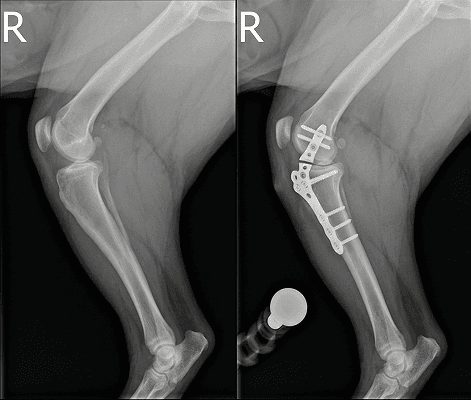

부러지거나 휘어진 뼈를 다루는 수술은 단순한 조립 과정이 아닙니다. 비비동물병원은 뼈가 스스로 붙을 수 있는 생물학적 환경(혈류)을 철저히 보존하고 국제 표준 원칙(AO)에 기반한 정교한 수술 계획으로 아이의 빠른 일상 복귀를 이끕니다.

최소침습(MIPO) 수술은 단순히 절개창을 줄이는 것이 아닙니다. 뼈가 스스로 붙는 데 필요한 주변 연부조직과 혈액 공급을 최대한 보존하여 '치유 능력'을 극대화합니다.

세계적인 정형외과 표준인 AO 원칙(AO Principle)을 엄격히 준수합니다. 아이가 체중을 싣고 걸어도 뼈가 흔들리지 않도록 생역학적 안정성과 기능 회복을 동시에 잡습니다.

부러진 뼈를 맞추기 위해 근육을 광범위하게 절개하지 않습니다. 수술 중 C-arm(실시간 방사선 투시 장비)을 활용하여 뼈의 정렬과 스크류의 위치를 실시간으로 확인하며 절개창은 최소화하고 수술의 정확도는 극대화합니다.

핵심은 '관절 하중의 정상화'입니다. 휘어진 다리를 미관상 이유로 교정하는 것이 아니라 관절 상태와 기형 정도를 다각도로 정밀하게 분석해 비정상적인 하중을 없애고 완벽한 뼈의 정렬을 되찾아줍니다.

수술 계획의 출발점입니다. 2방향(직교) X-ray를 통해 골절의 양상과 관절 침범 여부, 각기형의 다각도 변형을 오차 없이 정확히 파악합니다.

무작정 수술실에 들어가지 않습니다. 아이의 골격 구조를 면밀히 분석해 가장 튼튼하게 버틸 수 있는 플레이트 위치와 치유를 돕는 최적의 수술법을 미리 설계합니다.

수술 중 C-arm(실시간 투시 장비)을 통해 뼈의 정렬을 직접 확인합니다. 절개를 최소화하여 연부조직과 혈류를 보존하는 최소침습(MIPO) 방식으로 뼈를 안전하게 고정합니다.